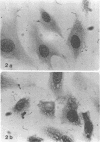

Spiroplasma mirum (suckling mouse cataract agent) was studied in an epithelial cell line AG-4676, derived from rabbit eye lens. Rabbit eye lens is a natural target tissue of S. mirum infection. The organism grew rapidly in this cell line, reaching titers of 10(7) to 10(9) color change units per ml at 7 days after infection. This is the same level as that achieved in SP-4 medium designed specifically for S. mirum. No lag period was apparent in growth in AG-4676. S. mirum did not grow in Dulbecco minimal essential medium-10% fetal bovine serum, the medium for AG-4676, indicating the need for cells or a cellular product. S. mirum-infected AG-4676 cells exhibited vacuolization and granulation and an increase in polynucleation compared with uninfected controls (36/100 versus 14/100, P less than 0.001). Infection significantly decreased the growth rate of AG-4676, especially late in the growth cycle. In a representative experiment, growth of AG-4676 at 11 days was reduced from 9 X 10(5) to 2 X 10(4) cells by S. mirum infection. S. mirum grew to high titers in conditioned medium of AG-4676, obtained from cell-free supernatants of 1- to 5-day-old AG-4676 cultures. This growth promotion was not due to osmotic conditioning of the medium. Preliminary characterization of this growth promotion substance showed it to be active after 0.22-micron filtration, heating at 56 degrees C for 30 min, freezing and thawing, and dilution at 10(-1) but not 10(-2). AG-4676-propagated S. mirum produced death or cataracts in suckling Wistar rats at the same frequency (55/60, 91.7%) as SP-4-propagated organisms (60/65, 92.3%).